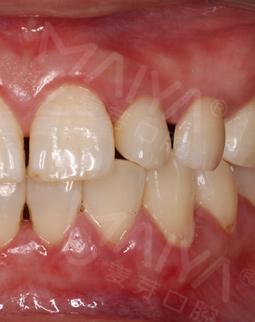

其实我更看重附加的价值,复诊了两次,没有额外收费,而且有专门人员提醒,医生态度一如既往的好,在麦芽种牙这个价格真的性价比很高了,毕竟材料、医生、种牙流程等等,我坚信种植牙是可以在我口内待一辈子的!而且就是第一次来的时候填个单子建个档案,后面我自己轻车熟路,直接去诊室,流程还是挺方便的,又节省时间。牙冠安装好了,很真牙没有什么两样,苦恼我多少年的问题终于在麦芽解决了!

拔牙种牙,就打麻药的时候有点感觉,其他的就是在牙椅上躺了一会就好了,手术时间很短,不到十分钟,种牙就结束了,真的种牙一点都不痛,种牙后的疼痛感也几乎为零,另外牙冠是定制的,需要等一段时间,用牙刷大小的东西扫了一下,就出现了模型,科技感很强!